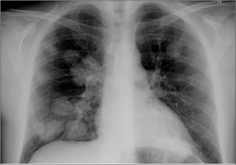

Figure 21.5 Multiple miliary nodules. Tuberculosis. These very small densities (2 mm diameter) are visible because the lung interstitium has hundreds/thousands of exceptionally tiny lesions superimposed one in front of another.